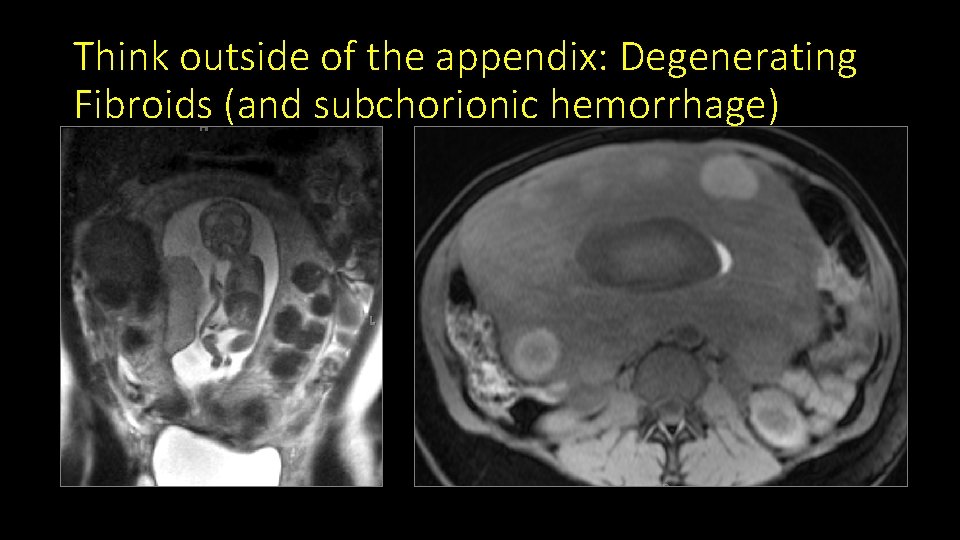

Think outside of the appendix: Degenerating Fibroids (and subchorionic hemorrhage)